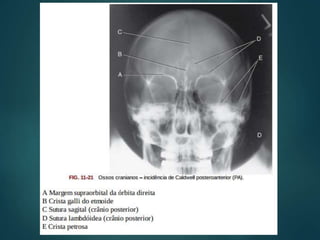

1- Parte basilardo osso temporal 2- Corpo do esfenóide 3- Crista Galli 4- Células Aéreas etmoidais 5- Seio Maxilar 6- Forame redondo 7- Seio Frontal 8- Asa maior do Esfenóide 9- Meato Acústico Interno 10- Sutura Lambdóide 11-Massa lateral do atlas 12- Asa menor do esfenóide 13- Processo mastóide 14- Septo ósseo do nariz 15- Processo Odontóide 16- Parte petrosa do osso temporal 17- Sutura sagital 18- Sela Turca 19- Fissura orbital superior 20- Face temporal da Asa maior